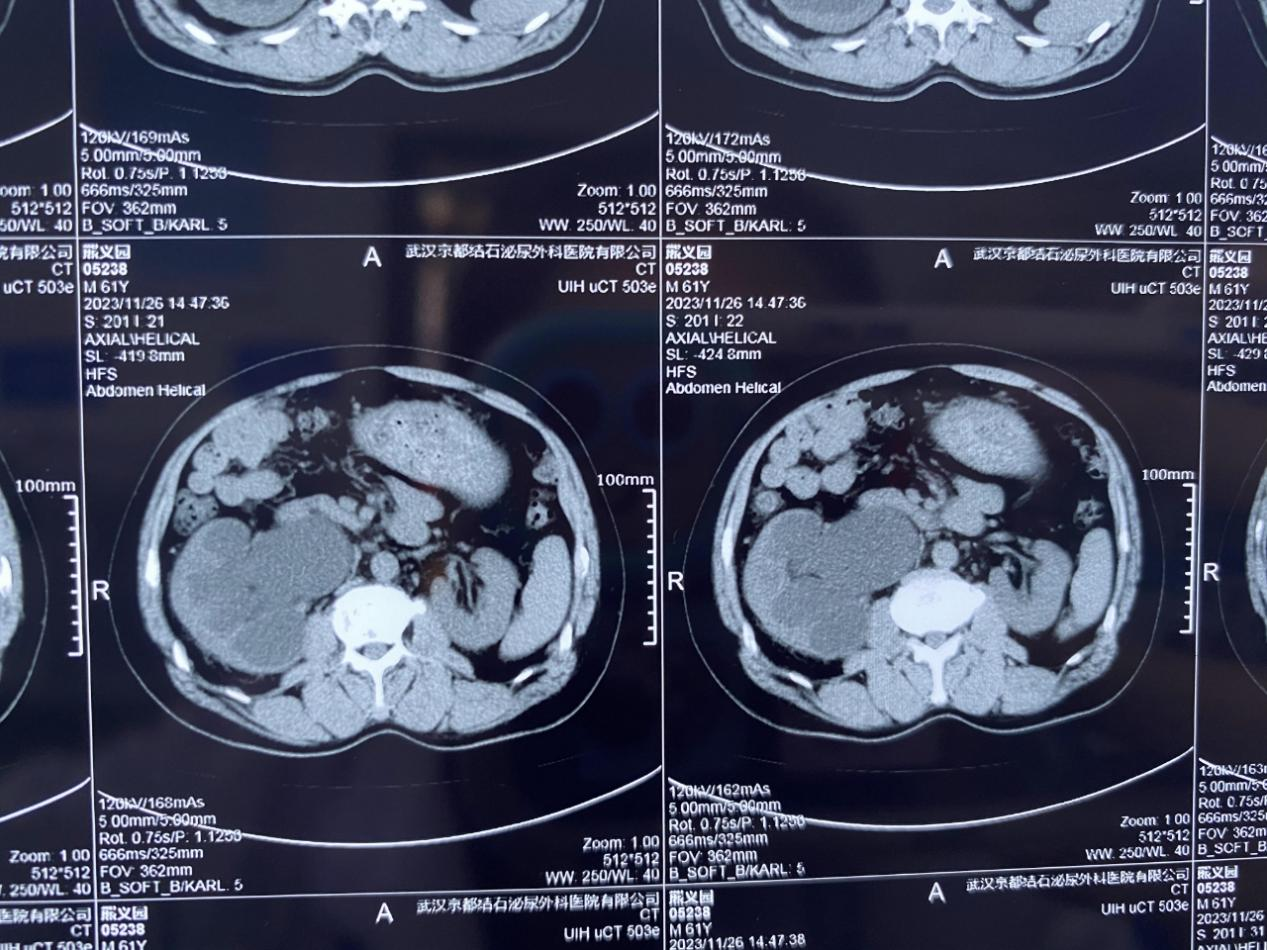

經(jīng)查,熊師傅的右輸尿管上段有多發(fā)結(jié)石梗阻,其中最大一顆結(jié)石有2.5cm,右腎已出現(xiàn)重度積水、腎功能不全等問題。該院泌尿外科主治醫(yī)師潘良超指出:“如果繼續(xù)拖延下去,右腎積水將會(huì)越來越嚴(yán)重,感染加劇,還會(huì)持續(xù)損害腎臟功能,屆時(shí)右腎可能將徹底“報(bào)廢”了,必須馬上手術(shù)處理?!?/span>

為了保住患者岌岌可危的右腎,在完善相關(guān)術(shù)前檢查后,該院泌尿結(jié)石團(tuán)隊(duì)為其制定并實(shí)施了電子軟鏡無創(chuàng)保腎取石術(shù)。手術(shù)全程1個(gè)多小時(shí),成功將其梗阻在輸尿管的結(jié)石清除取出,積水問題也得到了有效緩解,右腎危機(jī)得以正式解除。